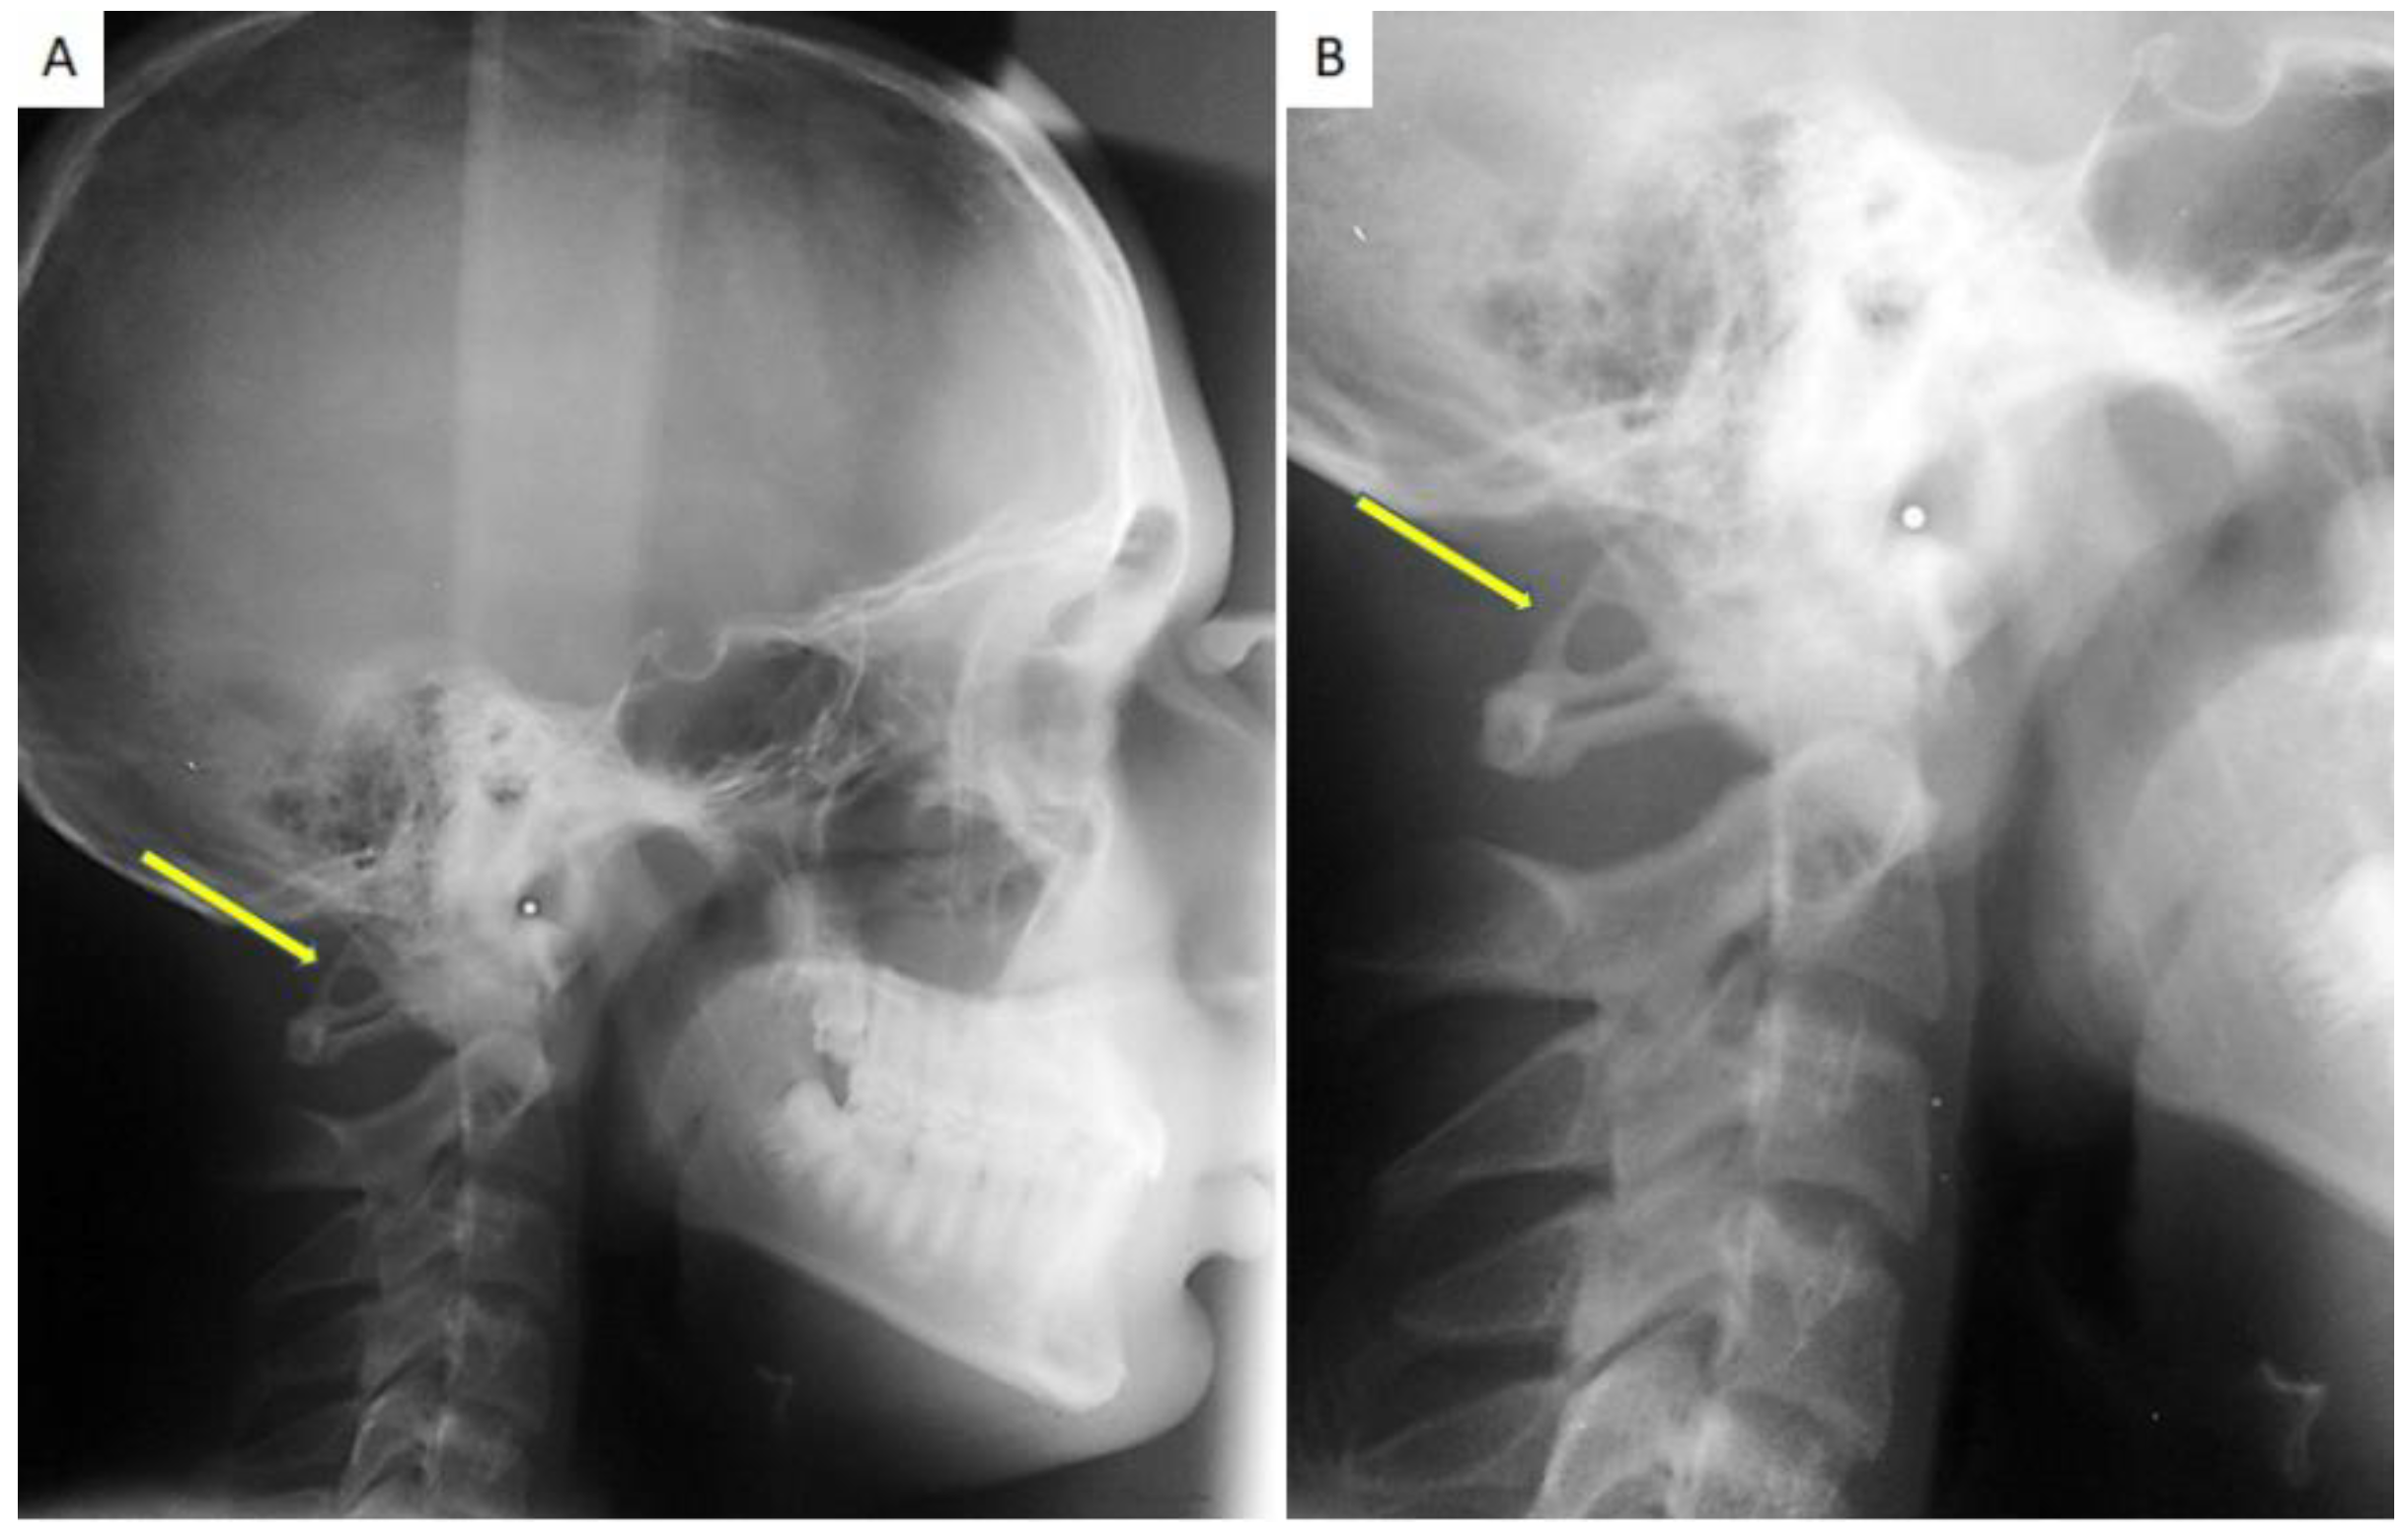

Calcification of the Atlanto-Occipital Ligament (Ponticulus Posticus) in Orthodontic Patients: A Retrospective Study